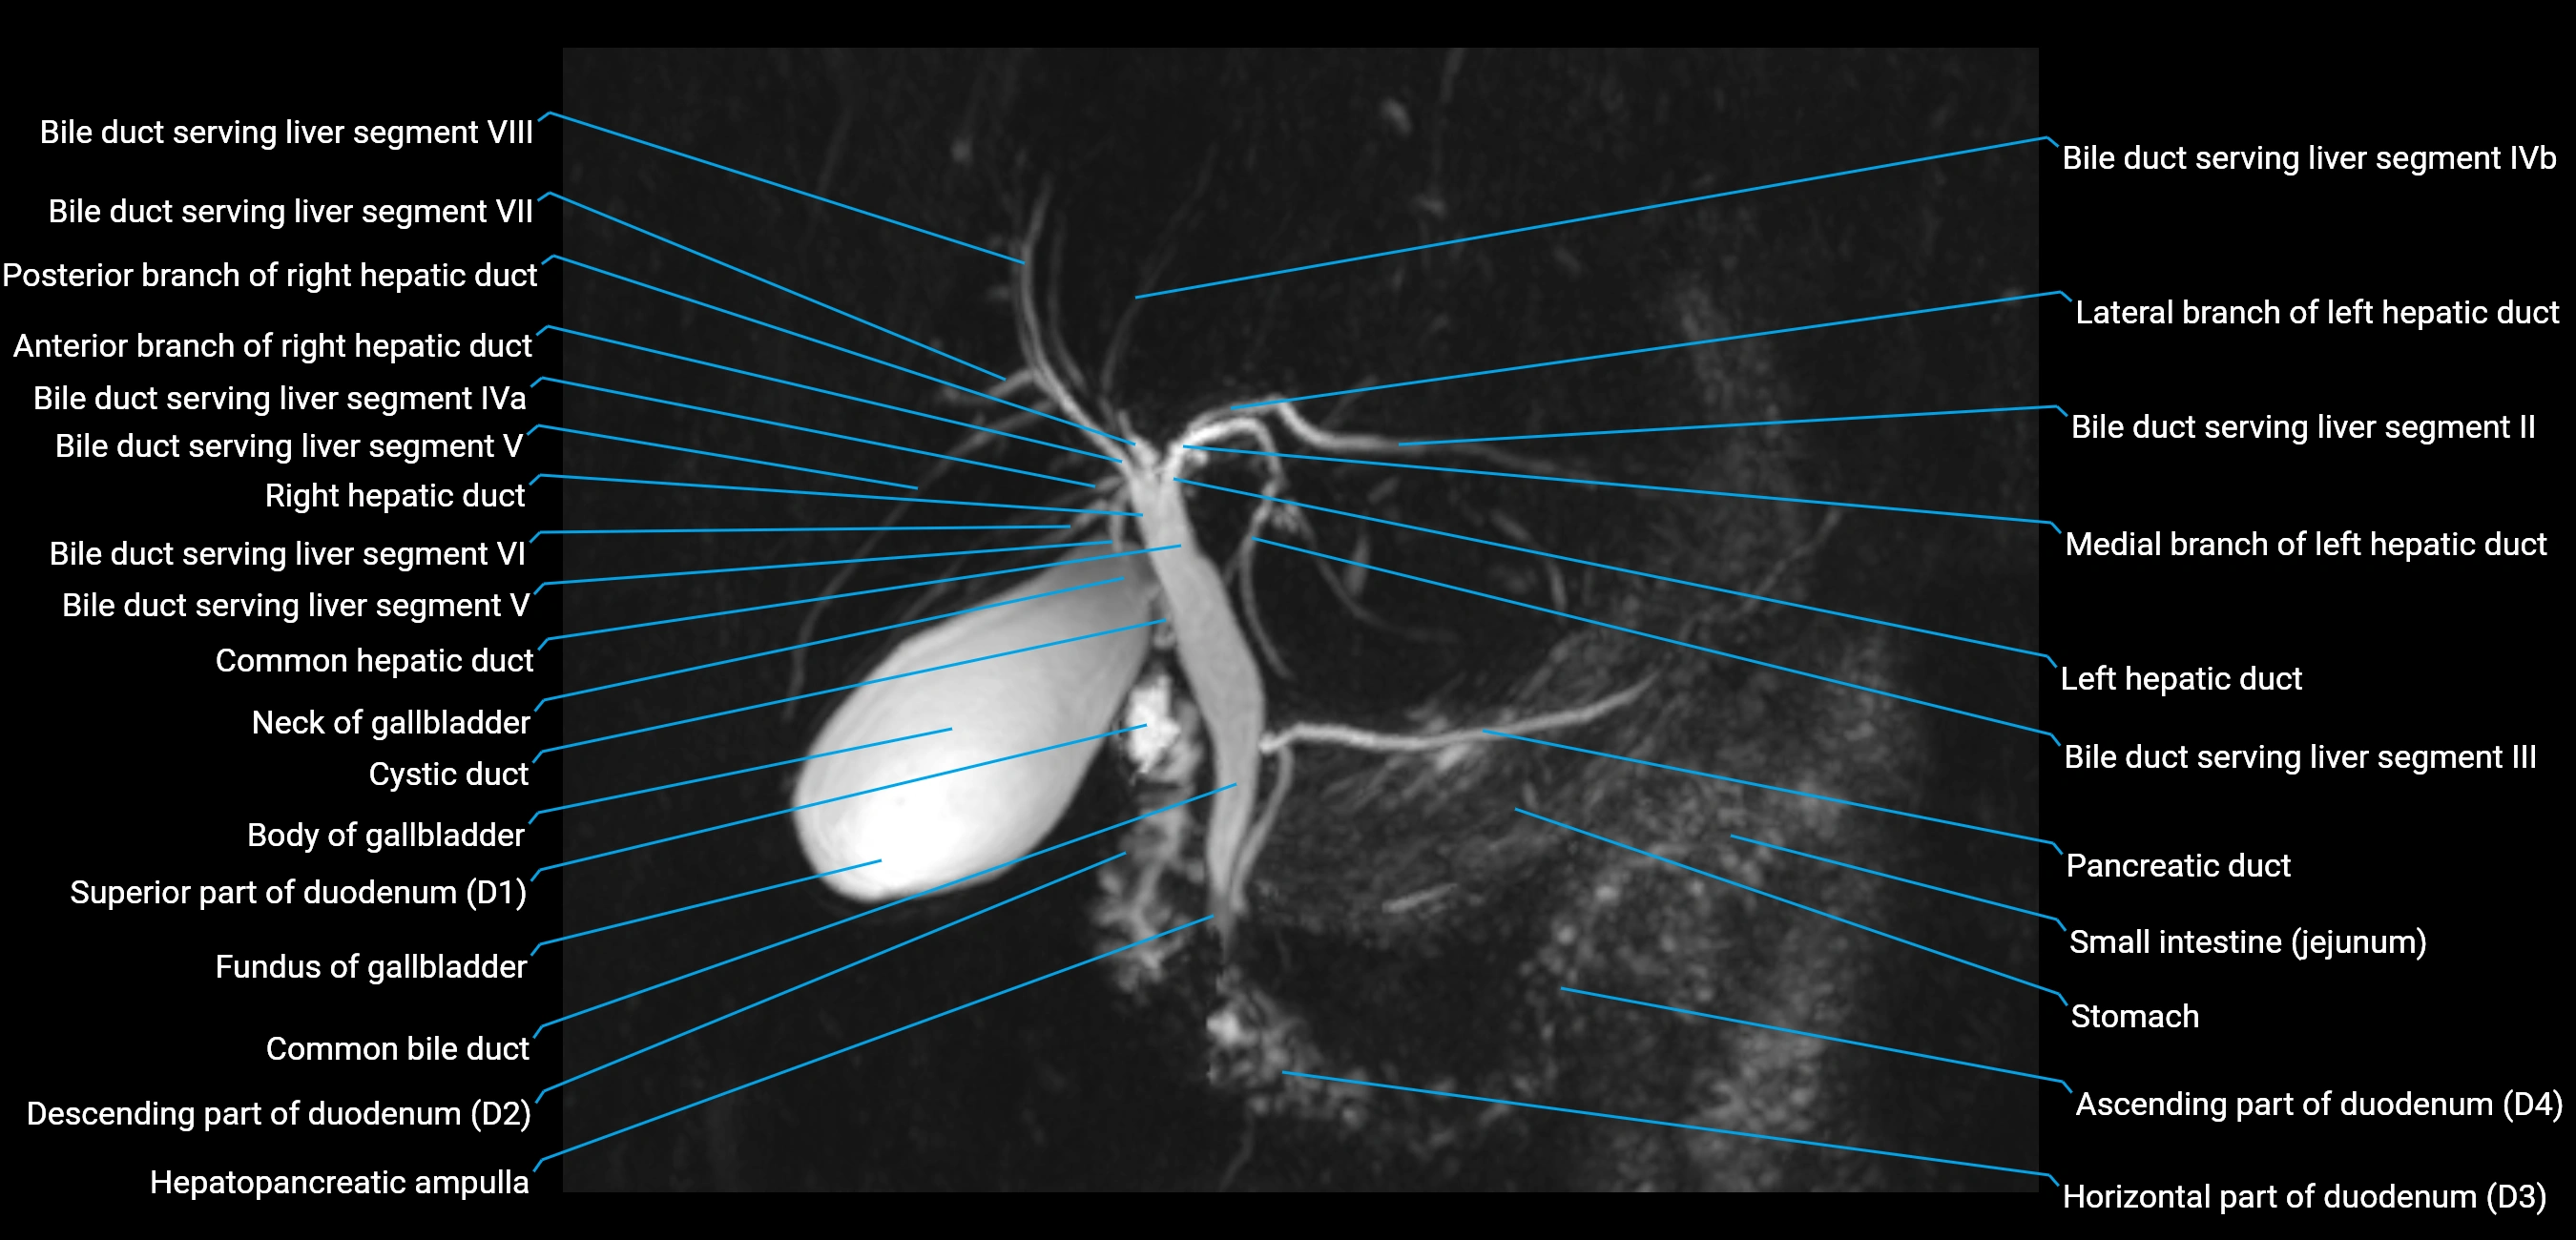

T2 TSE Fat-Saturated 3D (MRCP sequence):

• Duct visualized as a continuous bright tubular structure joining or parallel to the main pancreatic duct

• Allows 3D reconstruction of ductal anatomy and variants

• Excellent for diagnosis of pancreas divisum

Thick-slab T2 Fat-Saturated HASTE:

• Shows the accessory duct as part of the biliary–pancreatic system in a projectional image

• Highlights communication with main pancreatic duct and opening into the minor papilla

• Filling defects (stones, strictures) seen as dark spots within bright fluid

MRI image

image